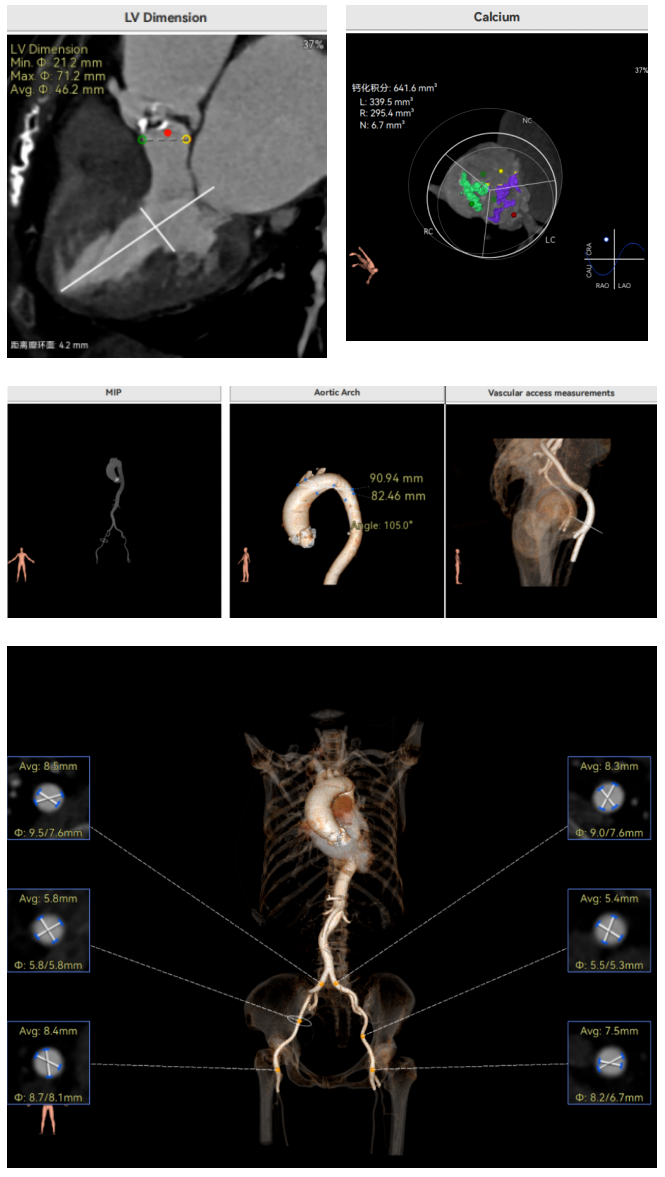

许金鹏教授 安徽省胸科医院 干瓣耐久首选之,15年承诺佑病患:随着病患的复杂性提高及TAVR二次手术窗口期的慢慢到来,摆在临床面前的是如何提升瓣膜使用的耐久性?预装干瓣的获批上市无疑为临床提供了全新的选择。预装干瓣摆脱了传统戊二醛保存的束缚,通过专利抗钙化技术及干式保存工艺打造了一款兼具“曲柔性”和“不沾钙”瓣叶的介入瓣,预期会有更耐久的使用寿命。此次病例患者小瓣环,Prostyle A®自膨瓣的收腰设计,为冠脉开口预留了“生命通道”,而平衡的收腰设计又很好的保证了开口面积,为小瓣环患者血流动力学提供的牢靠的保障。 期待这样一款基于临床需求的性能平衡的耐久干瓣,护佑 TAVR广大患者的全生命周期管理! 患者病史 主要诊断:非风湿性主动脉瓣狭窄(重度);非风湿性主动脉瓣关闭不全(中度);非风湿性二尖瓣关闭不全(中度);心脏扩大(左房明显扩大、左室略大);肺动脉高压(估测肺动脉收缩压约 39mmHg);胸椎压缩性骨折(T9 椎体,考虑新鲜);肺部阴影(两肺慢支改变、多发结节);胆囊术后; 入院检查:BP 109/60mmHg、心率 77 次 / 分(律齐),神清精神可,口唇不绀。 术前超声提示 主动脉瓣钙化并狭窄(重度)伴反流(中量),Vmax509cm/s,PGmax105mmHg;升主动脉增宽;左房明显增大,左室略大;二尖瓣关闭不全伴反流(中+量);瓣尖轻微增厚;室间隔增厚; 术前CT 三叶瓣(L-N融合,功能型二叶瓣),瓣叶增厚中度钙化,钙化主要分布在左冠窦瓣叶边缘及左无融合处、右冠瓣叶基底及边缘,主动脉瓣环径22.2mm,LVOT21.1mm,呈略直通型;双侧冠脉开口高度可,窦部空间大,VTC距离够,预估冠脉低风险,STJ、升主动脉内径可;左室内径可,主动脉水平夹角47°,非横位心。主动脉弓角弓距可;外周入路无明显迂曲,无钙化,两侧股动脉内径可,均可通过20F大鞘,右股低分叉。 手术策略 推荐右侧股动脉为主入路,左侧股动脉为辅助入路,使用20F大鞘,右股分叉上方1cm穿刺。推荐选择AV23瓣膜,18mm球囊预扩,最终理想位置瓣下2mm。 手术过程 在右股动脉穿刺建立通路后,顺利送入大鞘,经食道超声及血管造影确认路径稳定。18mm球囊预扩后评估冠脉灌注良好,后将Prostyle A® AV23瓣膜精准释放于目标位置,超声显示无瓣周漏,术后即刻造影显示无明显反流,导管测平均跨瓣压差8mmHg,心功能明显改善,患者生命体征平稳。 主动脉根部造影 18号球囊预扩 输送器顺利过弓 迅速锚定,平稳释放至工作位 最终造影,位置形态良好,无瓣周漏 Prostyle A®预装干瓣——助力临床最优化解决方案 预装干瓣 便捷顺安:金仕生物专利抗钙化技术运用纳米技术去除组织内的细胞碎片和磷脂,封闭游离醛基,从根本上阻断了瓣膜钙化的多项因素,显著提升了瓣膜的耐久性;同时,相比较传统戊二醛保存方式,干式存储最大限度的保留心包的亲水亲油平衡,还原组织天然曲柔性,进一步保障了瓣叶开合,保证长期耐久性; 流入端桶状设计:流入端桶状的设计,迅速稳定锚定,减少手术时间的同时进一步保障了术中安全; 平衡的收腰设计:该病例左冠高度10.8mm,AV23瓣膜的平衡收腰设计既确保了冠脉开口安全性,又保证了EOA,有效降低了循环崩溃风险,而术后8mmHg的压差的表现更加证明了优秀的血流动力学,进一步提高了瓣膜的耐久性。 专家简介 许金鹏 安徽省胸科医院(点击查看专家详细简历) · END ·